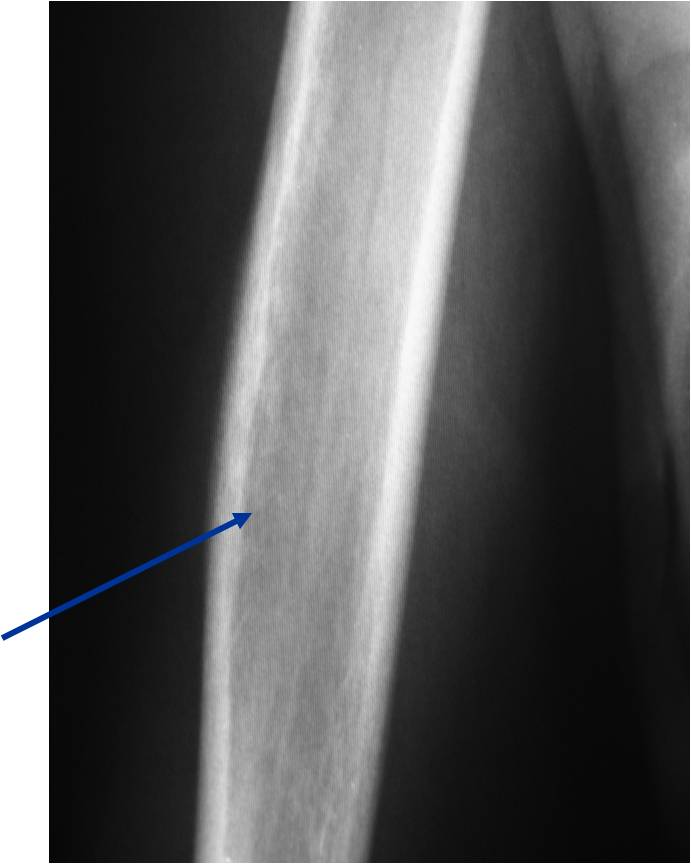

- Permeative or moth eaten bone destruction (55%)

- Metadiaphysis (75%)

- Periosteal reaction—may look benign

- Interrupted or solid single layer (66%)

Permeative Moth eaten Lesion

Permeative Lesion

Permeative/Moth eaten lesion Reactive sclerosis (mixed lysis and sclerosis) Slight periosteal reaction